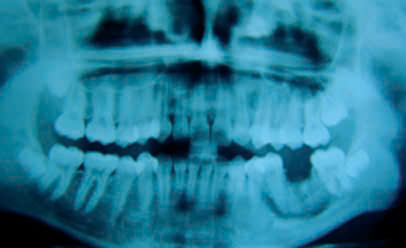

Hình 2: Viêm tủy xương hàm tại vị trí răng 36 sau điều trị nội nha và được nhổ bỏ6

Điểm chung của những ca lâm sàng này là bệnh nhân sử dụng arsenic trong điều trị tủy để giảm đau nhưng khi ra về bệnh nhân gặp phải cơn đau dữ dội và phải quay lại phòng khám để nhổ răng. Tuy nhiên, tình trạng tổn thương đã lan ra ngoài xương hàm.